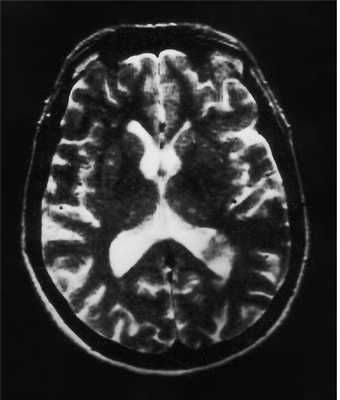

(б) MPT, FLAIR, аксиальный срез: у того же пациента в структуре коры визуализируется гипоинтенсивное объемное образование.